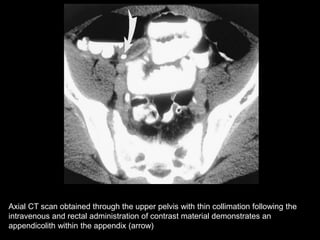

Axial CT scan obtained through the upper pelvis with thin collimation following the

intravenous and rectal administration of contrast material demonstrates an

appendicolith within the appendix (arrow)

Axial CT scanobtained through the upper pelvis with thin collimation following the intravenous and rectal administration of contrast material demonstrates an appendicolith within the appendix (arrow)